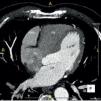

We report the case of a 58-year-old hypertensive man referred for a cardiology consultation due to atypical chest pain. The clinical examination was unremarkable. An electrocardiogram demonstrated sinus rhythm and incomplete right bundle branch block. He had an ambulatory echocardiogram that was described as normal. An exercise test was negative for ischemia and showed intermittent complete right bundle branch block. To exclude coronary disease a contrast computed tomography (CT) scan was performed that revealed a saccular aneurysm of the lateral free wall of the right atrium measuring 45 mm×45 mm×43 mm (Figures 1 and 2). There was no evidence of coronary disease. Given the CT findings, transthoracic echocardiography was repeated and revealed a cystic, pulsatile structure in continuity with the free wall of the right atrium through a narrow neck (Figure 3) permitting low-speed two-way flow, subsequently confirmed by injection of Sonovue® contrast. No cardiac thrombi were visualized. The tricuspid valvular apparatus and right ventricle were morphologically normal, as was biventricular systolic function. Similar findings were visualized on the transesophageal echocardiogram.